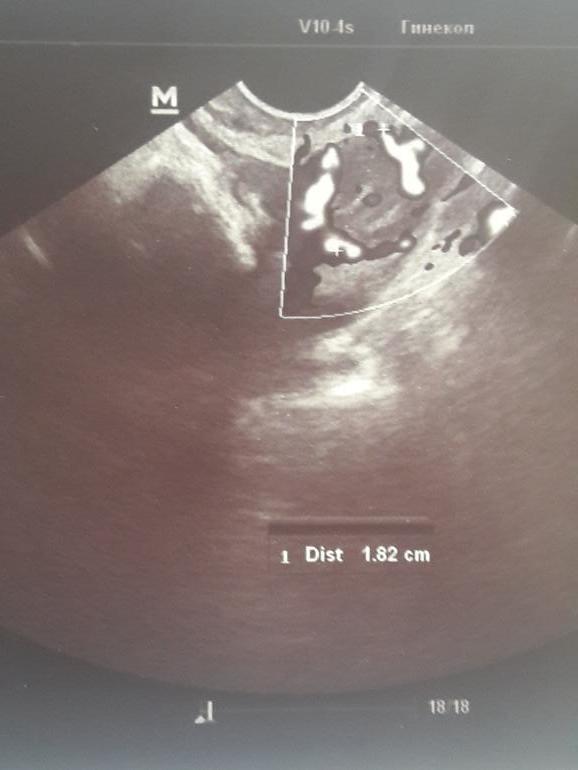

а вот это узи-похоже на ваше-просто с доминантным фолликулом

Оно видите какое-на всех узи оно серое с какой то темноватой точкой внутри..а у вас оно черное

фолликул, так как жт серое с вкраплениями.